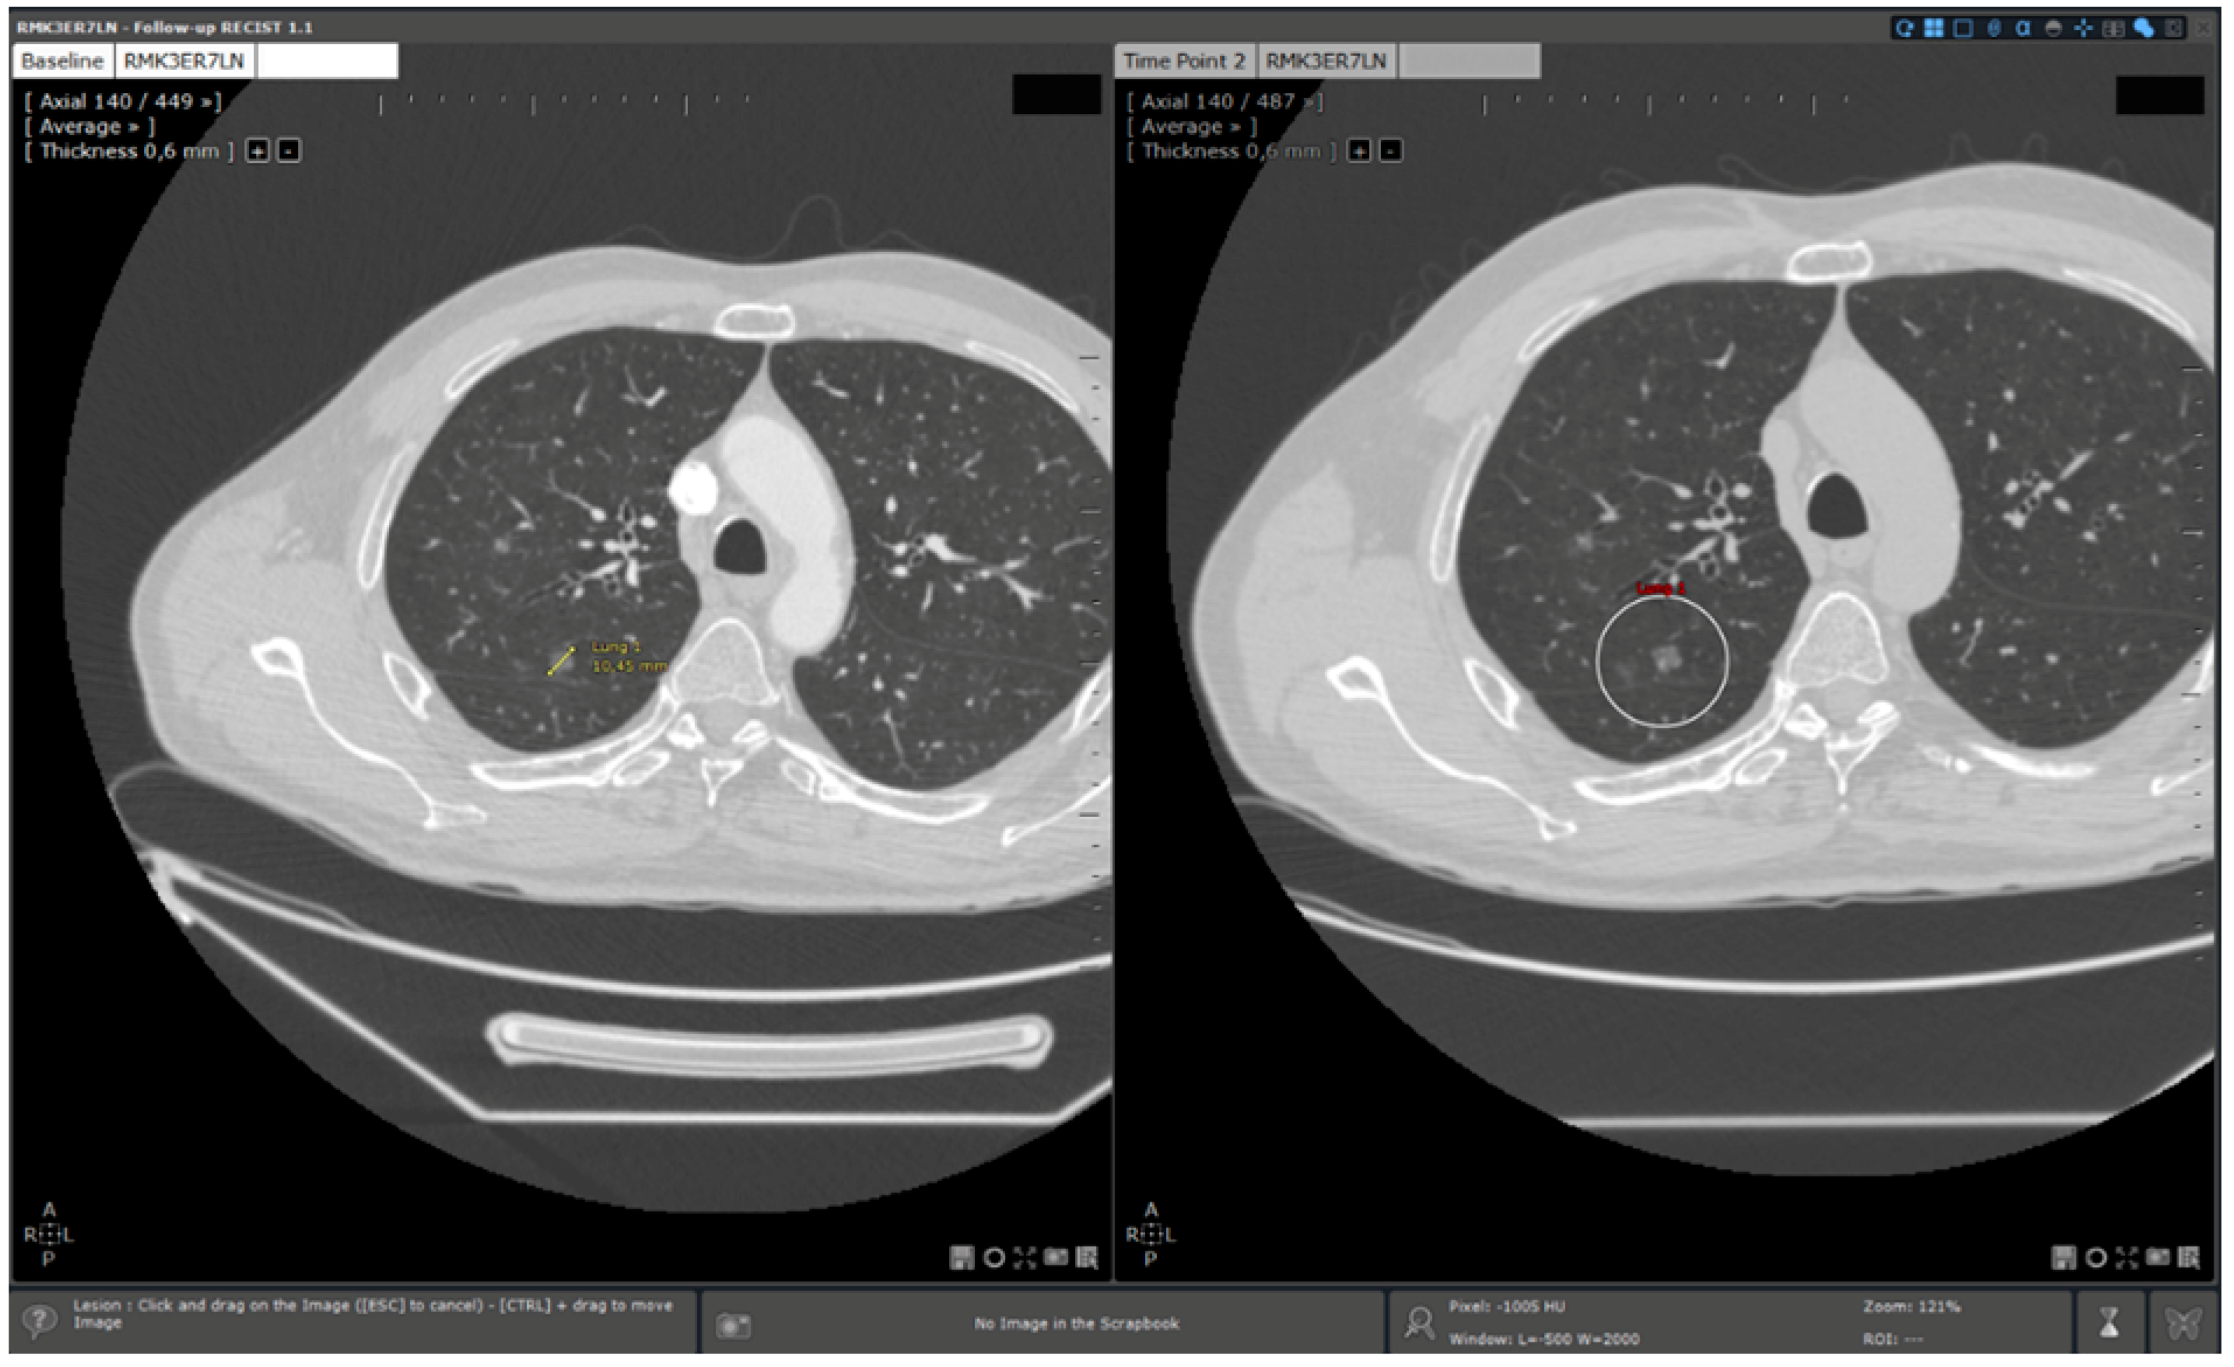

- 3D target matching technology to facilitate lesion localisation in the follow up study.

| Step 3 | Target localisation on baseline study | Manual | Automated |

| Step 4 | Target localisation on follow up study | Manual | Automated |